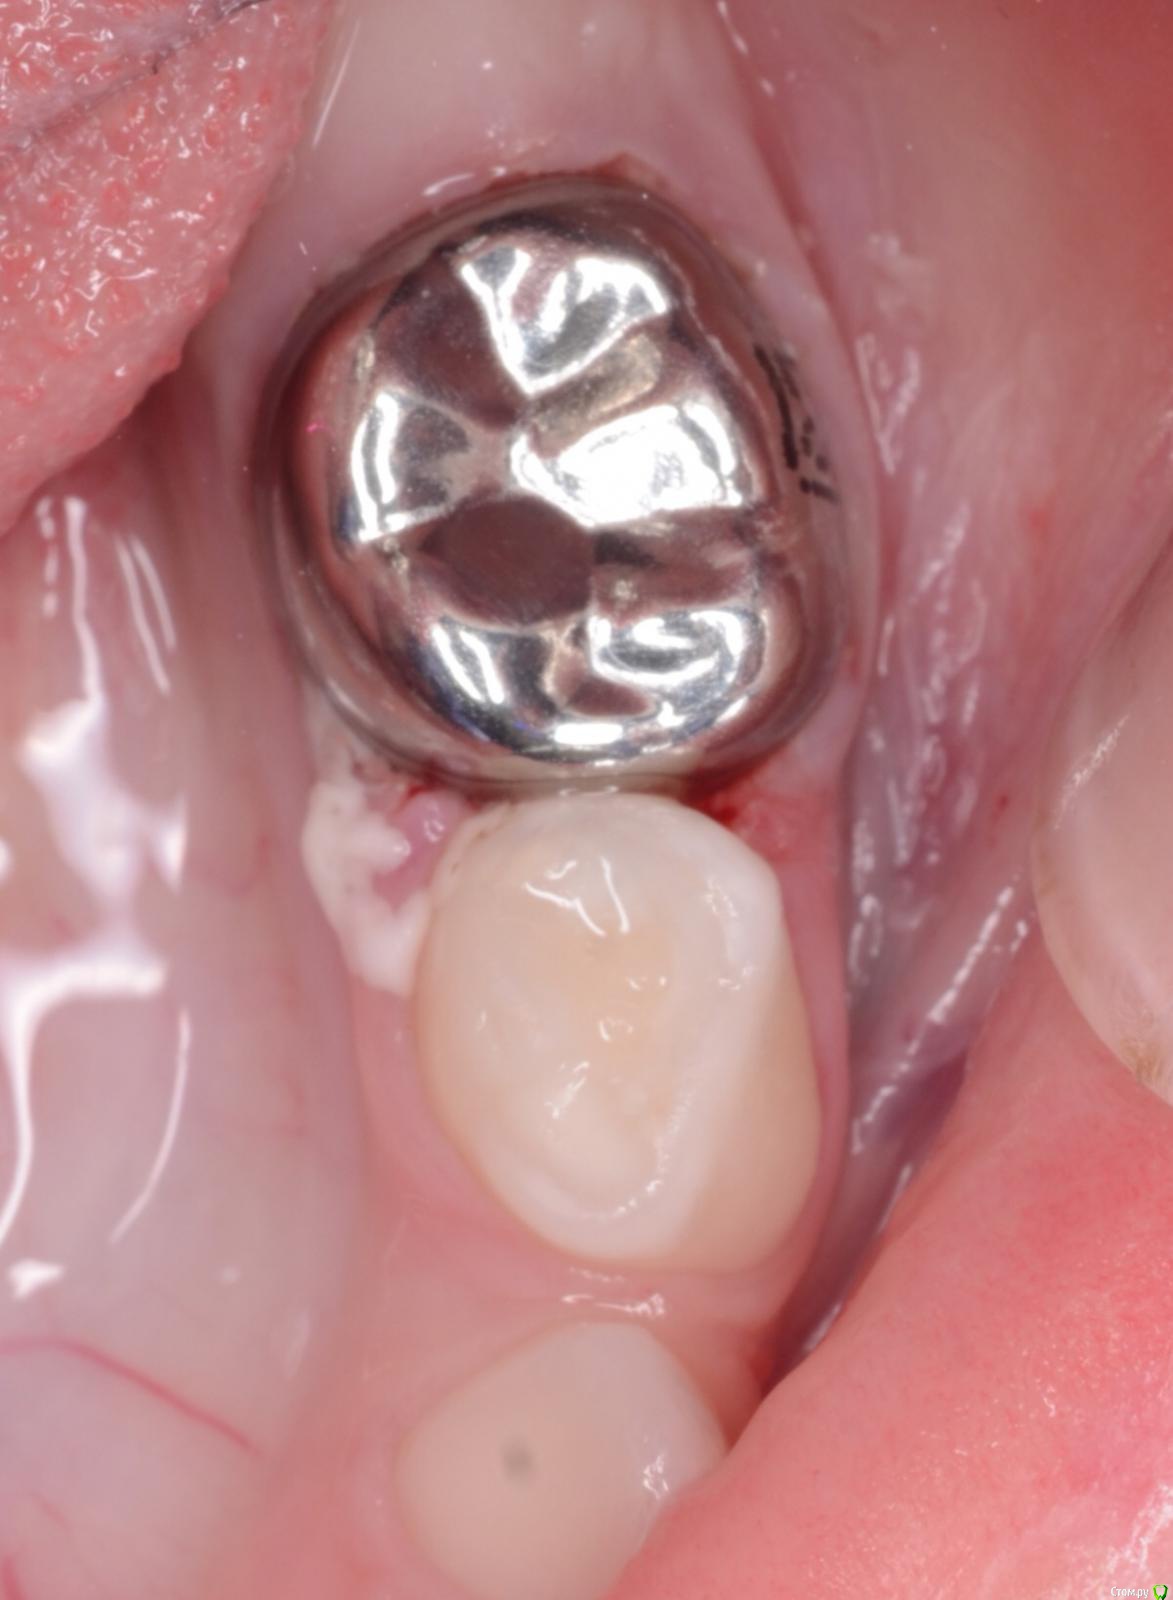

CRAZYDUCK Опубликовано 30 мая, 2018 Автор Поделиться Опубликовано 30 мая, 2018 (изменено) В этом случае немного видно преп под коронку . Описание случая ниже .B9CDEEE8-69F9-4F9D-B72C-1663ADE5EECD.bmp Изменено 30 мая, 2018 пользователем CRAZYDUCK 7 Ссылка на комментарий

CRAZYDUCK Опубликовано 30 мая, 2018 Автор Поделиться Опубликовано 30 мая, 2018 Лечение 7.4 . Необратимый пульпит 7.4 зуба . В данном случае хорошо видно , что после ампутации гемостаз не наступает ( полость зуба заполнена кровью). Позже выложу случай со спонтанным гемостазом . Одного критерия , который бы со 100% вероятностью помогал понять , что нужна экстирпация нет . ❗Жалобы —если была самопроизвольная боль , которая не была связана с приемом пищи или выраженное последействие после пищи, боль купировалась приемом обезболивающего . Болит так , что ребёнок плачет . Самопроизвольная боль есть - скорее всего экстирпация ( если не удаление зуба).❗RVG если полость пульпы сообщается с кариозной полостью , то скорее всего экстирпация - учитывать проекцию тоже нужно .❗Гемостаз должен наступить через 4-5 минут после ампутации, если его нет - экстирпация .В данном случае боль была только кратковременная после приёма жесткой пищи . Преп, экстирпация ( Sxмашинный протейпер ), потом до 25.02 ручными , гипохлорит 3%, Йодотин в каналы , IRM культя , коронка фиксирована на Айрекс Цем . Обратите внимание - во время обработки зуба под Коронку - все в хлам и платок и десна . Предупреждаем родителей о дискомфорте , связанном с травмированием десны. 7 Ссылка на комментарий